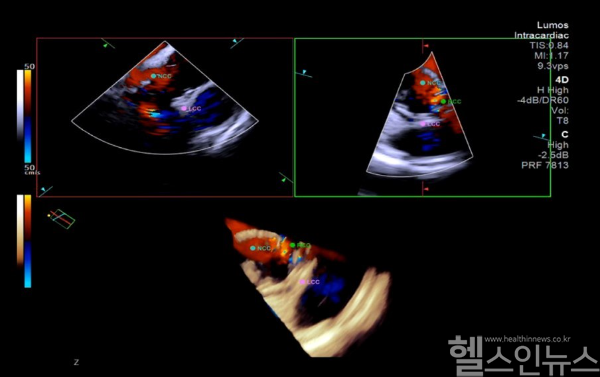

임홍의, 조준환 순환기내과 교수는 지난 13일, 국제심장혈관 시술 영상포럼 ‘K-imaging 2025’ 라이브 시술 세션을 통해 4D 심장내 초음파를 이용한 TAVI 시술 두 건을 성공적으로 마쳤다. 해당 시술은 13개국 심장중재 전문의들이 지켜보는 가운데 실시간으로 진행돼 큰 주목을 받았다.

TAVI는 허벅지 동맥을 통해 인공 판막을 삽입하는 시술로, 고령 환자의 중증 대동맥판막 협착증 치료에 주로 사용된다. 하지만 시술 난도가 높고 합병증 위험도 커 고도의 기술이 요구된다.